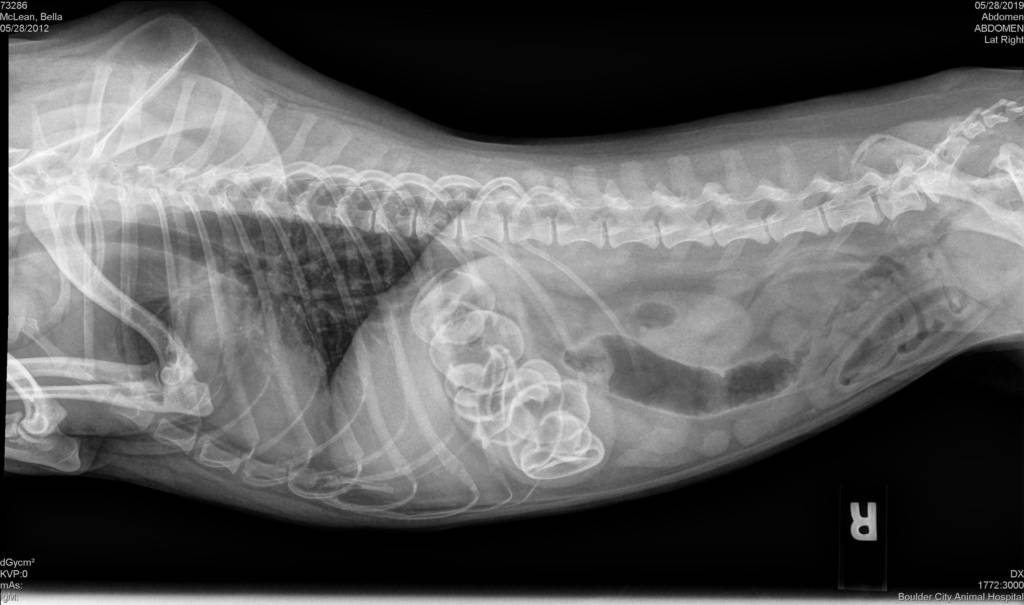

2019 They Ate What?! X-ray Contest winnersThey Ate This: Check out the winner, runners-up, and honorable mentions September 30, 2019 < Previous Entry Next Entry > Pages: 1 2 3 4 5 6 7 8 9 10 11 12 13 14